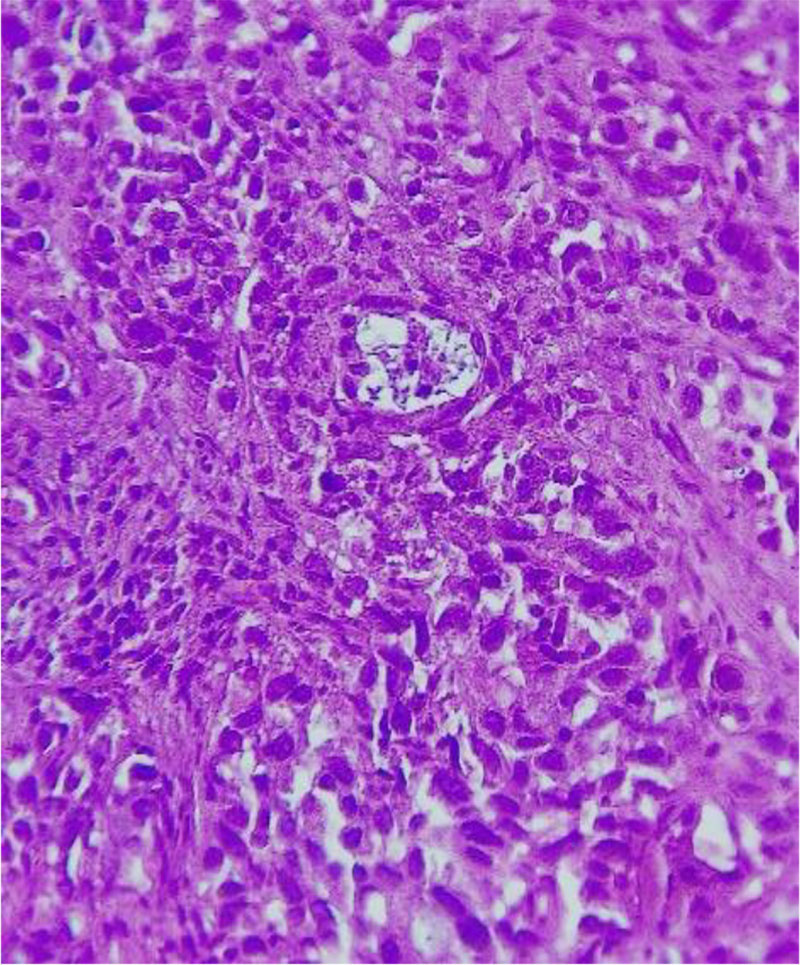

Microscopic examination classifies squamous cell carcinoma in two categories: keratinizing or non-keratinizing. The patient presented the keratinizing variant, which is made up of sheets or nests of polygonal cells with intercellular bridges (desmosomes) and keratin pearl formation. The neoplastic squamous cell has large, hyperchromatic nuclei with coarse chromatin, the nuclear and cellular pleomorphism being variable. Concerning the degree of differentiation, the pleomorphism of the tumor with pseudo-glandular structures and <75% undifferentiated structures (Fig.1.) and <25% keratinization allowed for it to be classified as a poorly differentiated squamous cell carcinoma (G3).

Fig.1. Poorly differentiated squamous cell carcinoma (G3).

Pseudo glandular area. H&Ex400

Source: Authors' own work